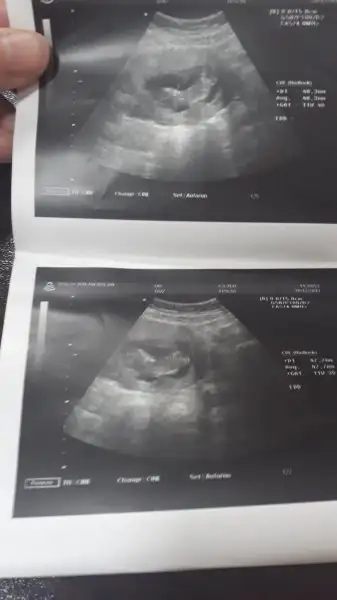

Canım bak ilk resimde kesenin etrafında beyaz bi yarım halka var ve çoğunlukla sol tarafta o halka plasenta bebeğin eşin yani pşasenta ne taraftaysa bebekte o tarafta oluyo yani bebek erkek gibi teoriye göre

Vayy. Ne kadar uzmanlaşmışsın kuzum bu işlerde saol canım , erkek ozaman minnak , anneler hisseder derler ama ben hissedemedim demekki bana kız gibi gelmişti çok şükür erkek de olur kızda ilk evladım olucak